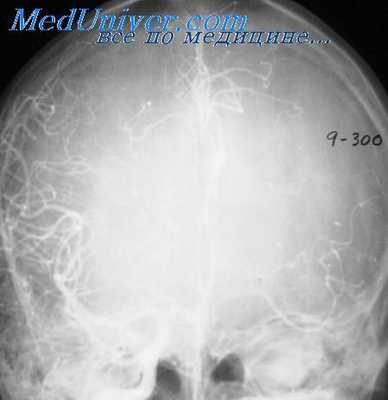

Пневмоэнцефалографическое исследование (ПЭГ) в свое время было общепринятым при эпилепсии. Сейчас оно применяется реже. Это связано с недостаточной информативностью его при определении локализации эпилептического очага и тем более при диагностике эпилепсии. ПЭГ способствует уточнению структуры эпилептического поражения главным образом при травматических рубцово-спаечных процессах.

При атрофических процессах его возможности в этом отношении значительно ниже. Здесь могут иметь значение выявляемые локальные изменения, например описанное нами ложкообразное расширение нижнего рога бокового желудочка, свидетельствующее об атрофии гнппокампа и соседних структур, нередко выявляемое при височной эпилепсии на стороне очага.

Гидроцефалия нижнего рога бокового желудочка выявлена нами у 42% больных височной эпилепсией. При этом у 44 из 50 больных данные ПЭГ коррелировали с результатами клинического и энцефалографического исследоваиий относительно латерализакии и у 41 —локализации поражения. Это показывает значительную диагности ческую значимость признака.

Говоря о методе пневмоэнцефалографии, следует обсудить принципиальный вопрос трактовки результатов исследования. Как известно, процент выявленных с помощью ПЭГ структурных изменений мозговой ткаии и оболочек мозга весьма высок. Соответственно возможностям метода изменения обнаруживаются в субарахноидальных пространствах и желудочковой системе мозга.